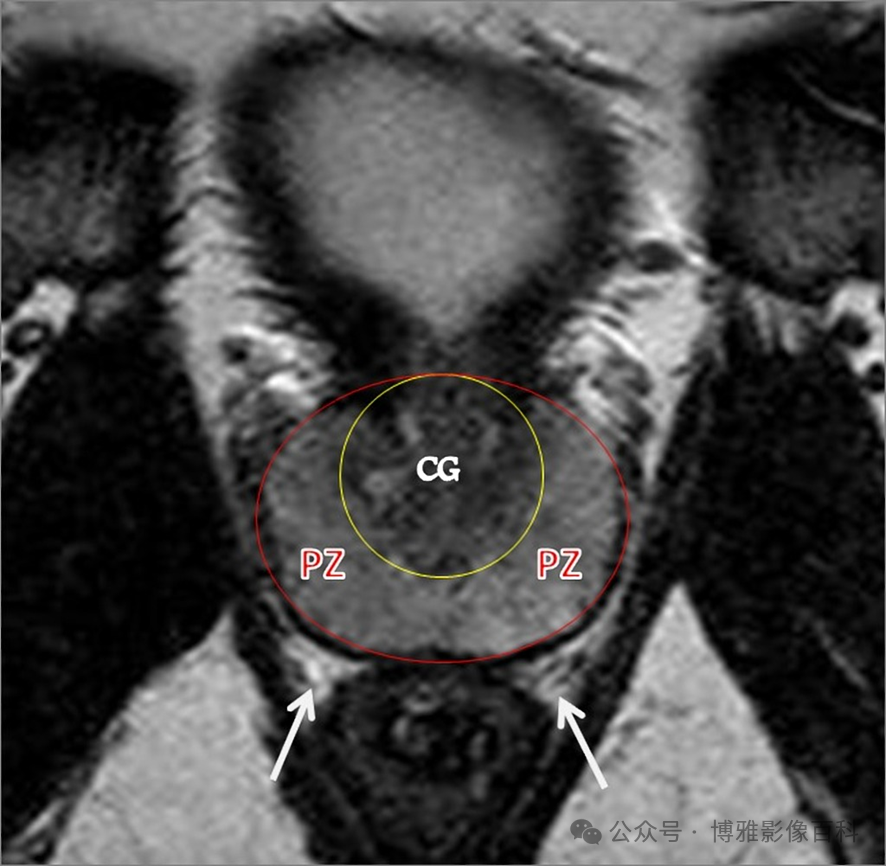

70-75% 的前列腺癌起源于外周带 (PZ)。该区域的后部可以通过直肠指检进行检查。

25% 的前列腺癌起源于移行带 (TZ)。极少数前列腺癌出现在中央带或前纤维肌基质中。

MR 解剖学

前列腺良性增生患者的轴向T2 图像,其他方面正常。外周带是一薄层均匀的高信号,边界清晰连续性的低信号包膜。移行带通常表现为不均匀中等信号,病灶被边界清楚的BPH良性前列腺增生结节所取代。精囊具有均匀T2高信号。未见淋巴结肿大。